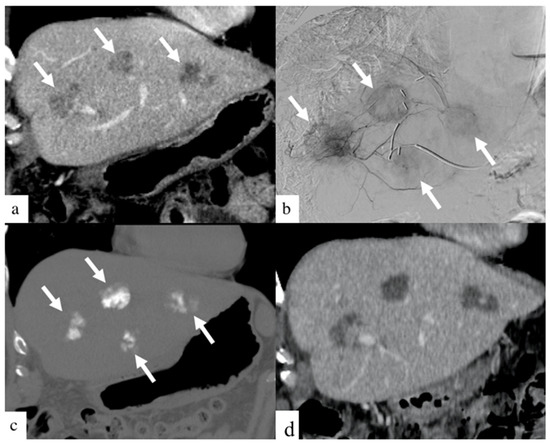

3. Results